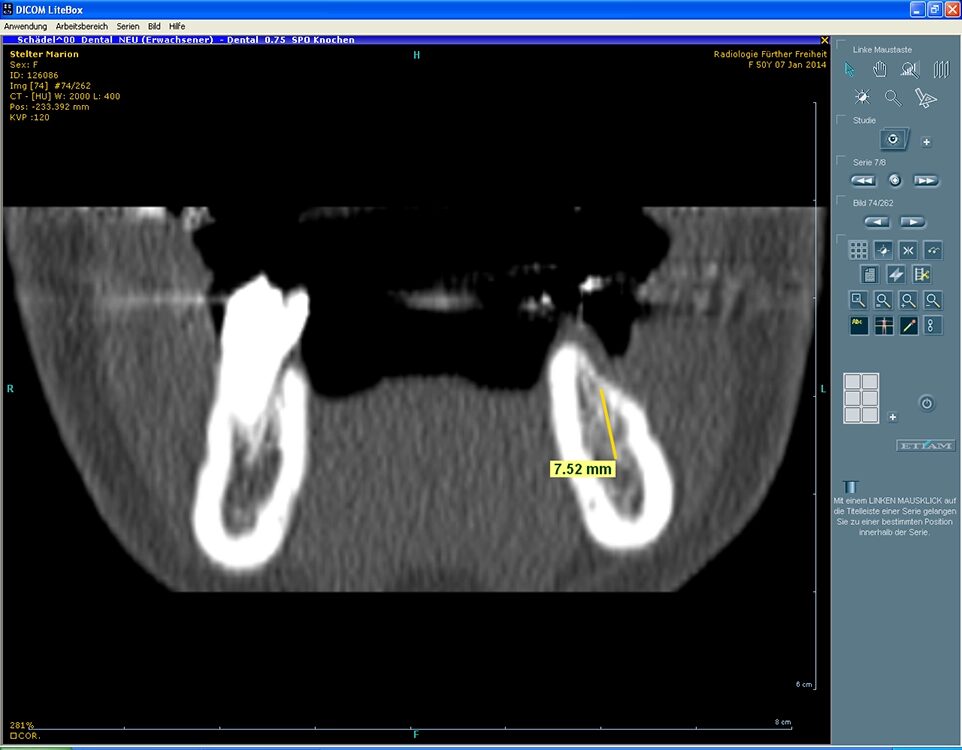

- Anatomische Information: Mehrinformationen sind die Nähe zum N. alveolaris, die Ausdehnung der Kieferhöhle und ihrer Septen, der Verlauf (insbesondere transversal) und die Mineralisation des Implantatknochens (nach Zahnextraktion) sowie die Positionierung des/r Implantate/s in Relation zu Nachbarzähnen (Abb. 9 und 10). Durch Schrägmessungen resultieren auch im DVT-Messfehler von bis zu 1 mm [5,6].

- Mindestabstand bei einwurzeligen Zähnen einschl. Prämolaren: 7 mm.

- Im Molarenbereich Implantatabstände von mindestens 11 mm (Abb. 11).

Häufig ist für die prothetisch ideale Implantatposition die lokale Knochenanatomie unzureichend, insbesondere bei Kreuzbiss oder langjährigen parodontalen Schäden usw. (Abb. 12 bis 14). Bestätigt die klinische Untersuchung diesen Verdacht, erfolgt eine 3D-Beurteilung der Knochenbreite mit individualisierter Implantatposition, ggfs. auch unter Verwendung durchmesserreduzierter Implantate. Alternativen Aufwand, Umfang und Kosten von Augmentation, Knochenentnahme oder Fremdmaterial mit Lappenmobilisation und möglicher Infektion vorab kalkulieren.